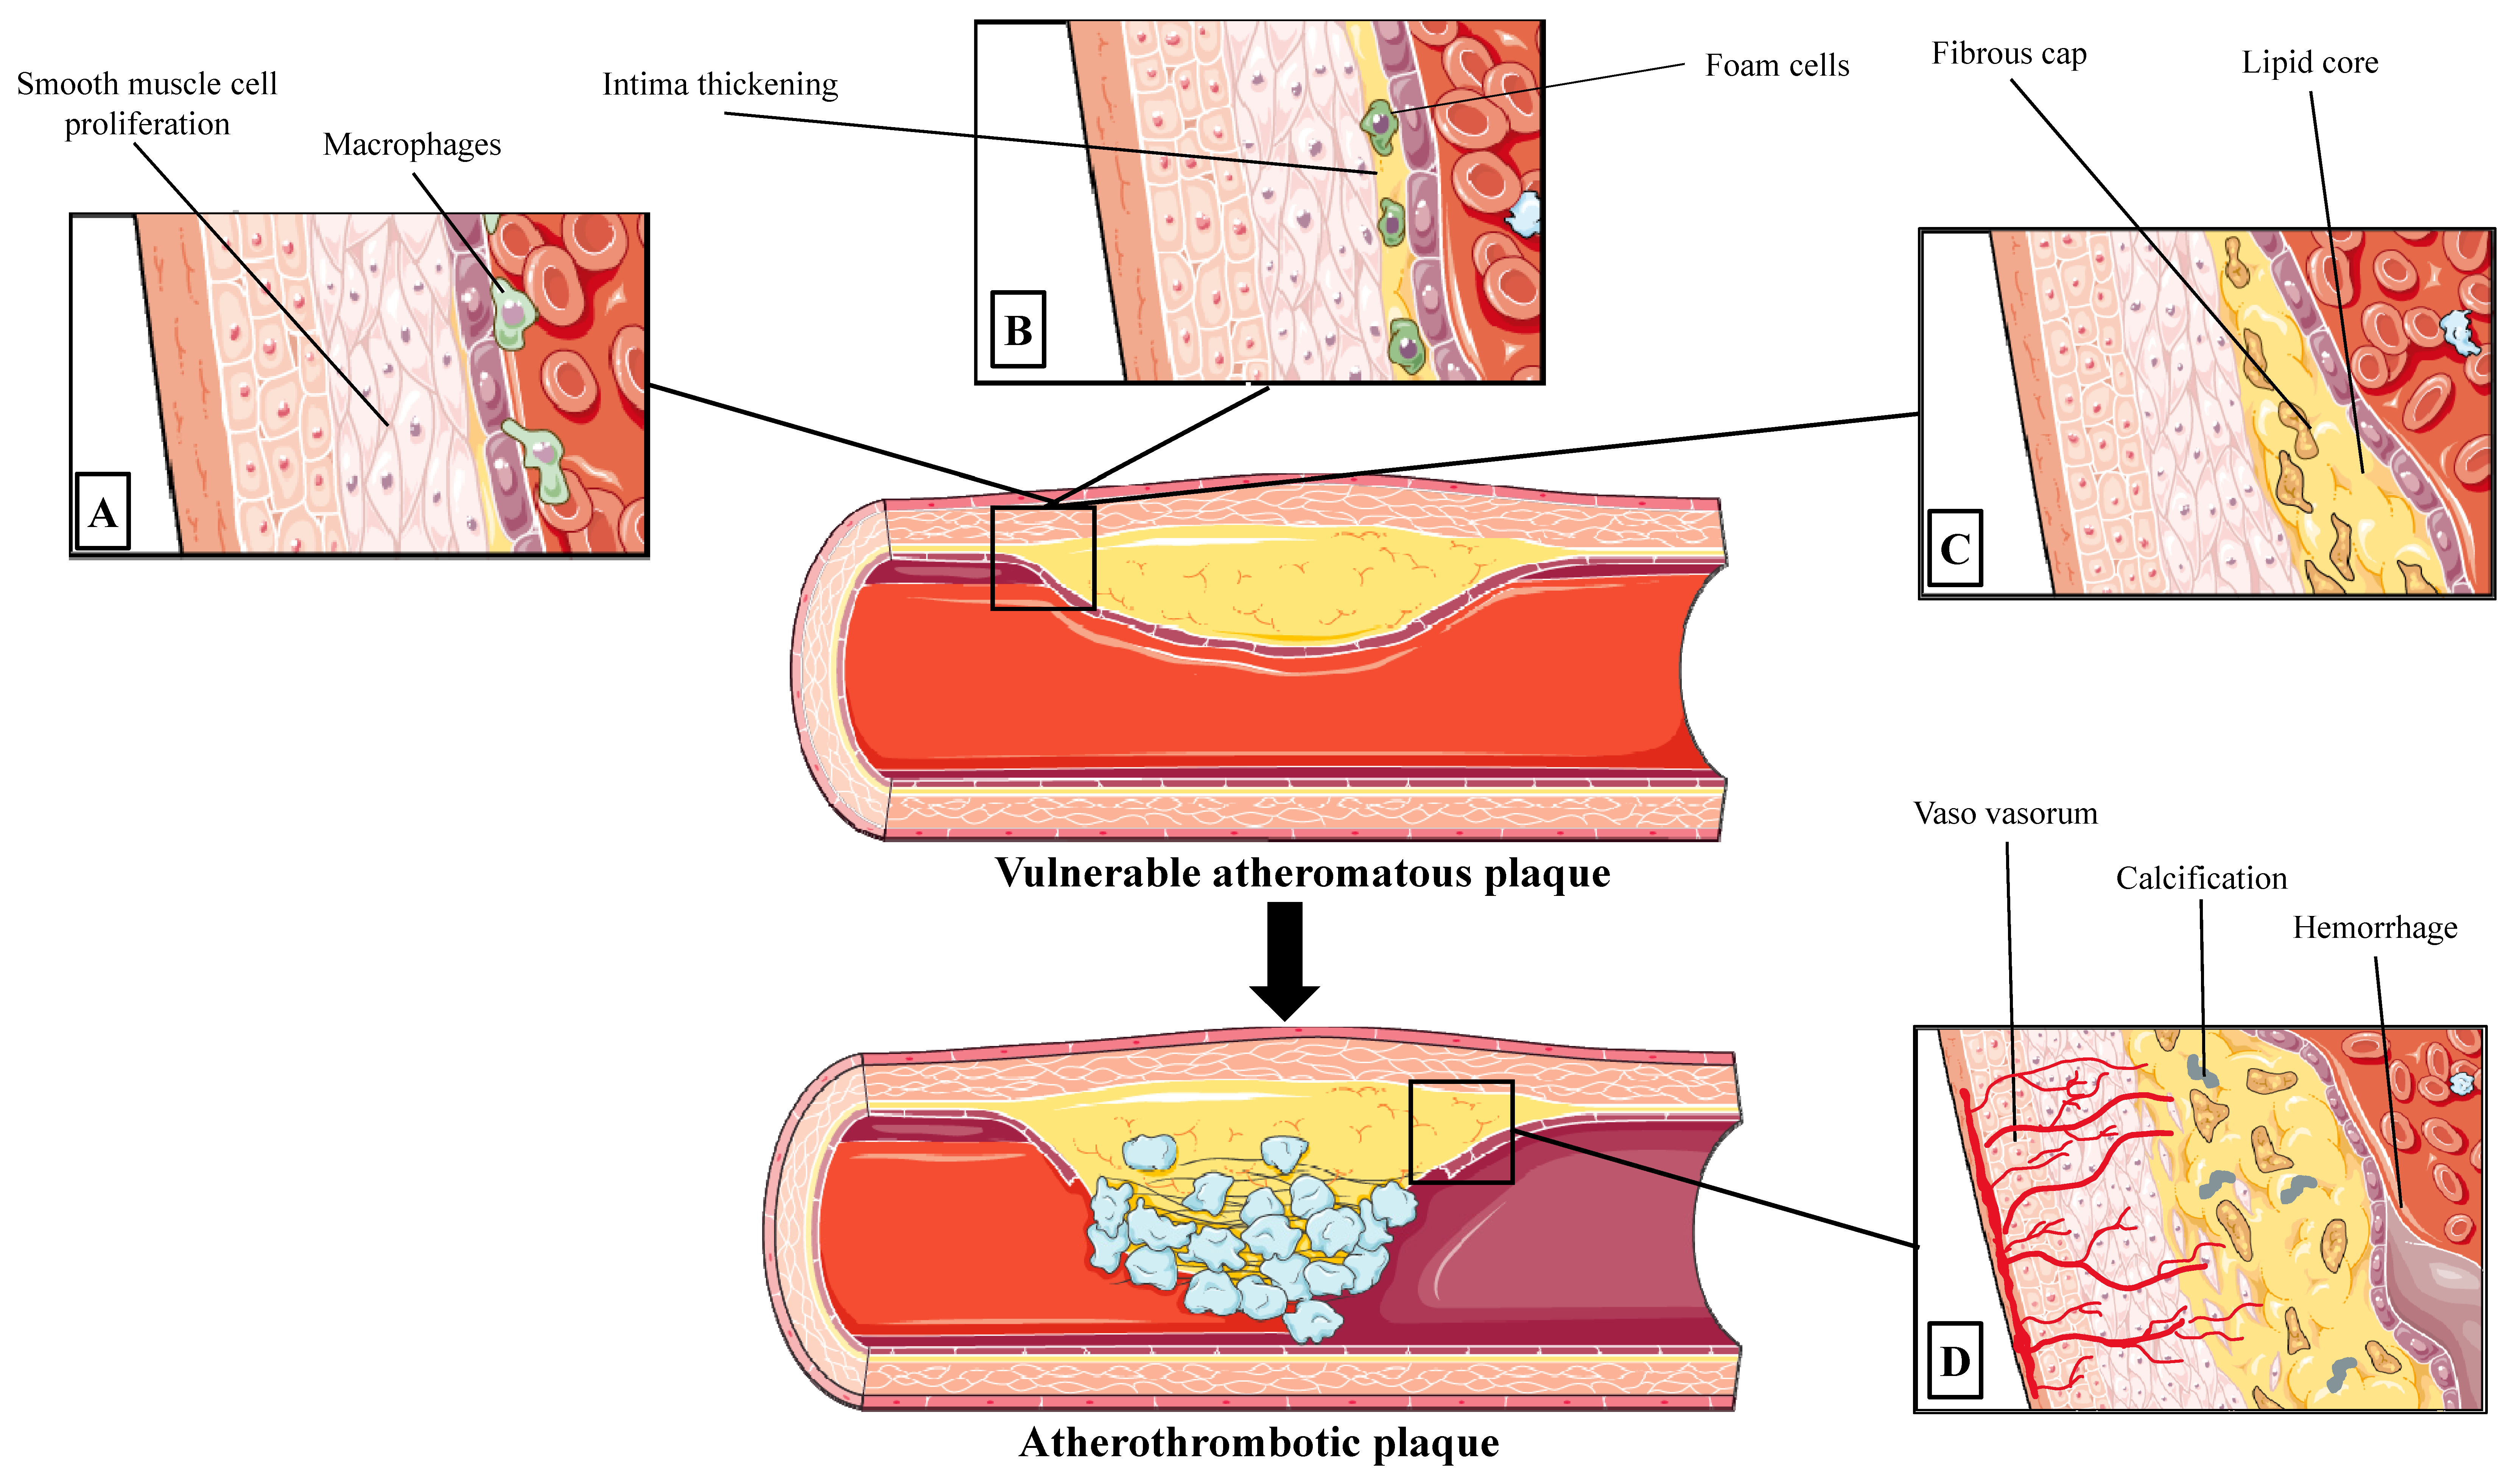

2.1. Progression to Vulnerable Coronary Atherosclerotic Lesion

2.2. Types of Atherosclerotic Lesion in Acute Coronary Syndromes